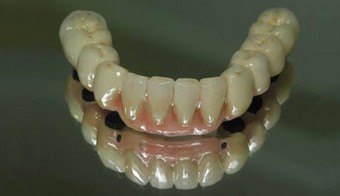

Pontes sobre Implantes

Os pilares implantares personalizados permitem-nos trabalhar da mesma forma do que sobre pilares dentários.

Ponte em zircónia cerâmica sobre pilares metálicos.

Ponte em zircónia cerâmica sobre pilares metálicos.

Pontes metalo-cerâmicas sobre pilares implantares.

Ponte metalo-cerâmica aparafusada sobre implantes.